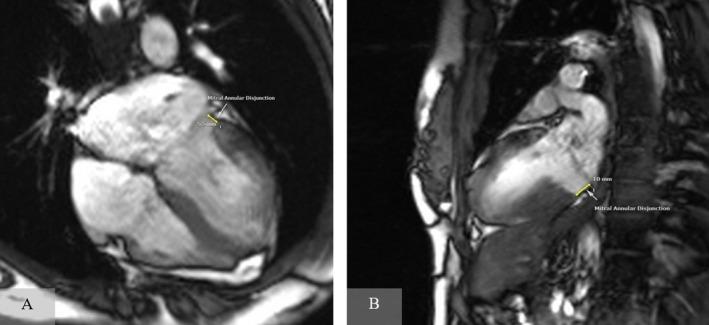

Mitral Annulus Disjunction Causing Ventricular Tachyarrhythmias in a Young Lady With Palpitations, Cardiac Ablation Terminated the Complaints.

Mitral annulus disjunction (MAD) is a rare but significant cause of ventricular arrhythmias in young patients. Timely diagnosis using cardiac magnetic resonance imaging and targeted management with catheter ablation can effectively control arrhythmias, improve patient outcomes, and prevent severe complications such as sudden cardiac death.